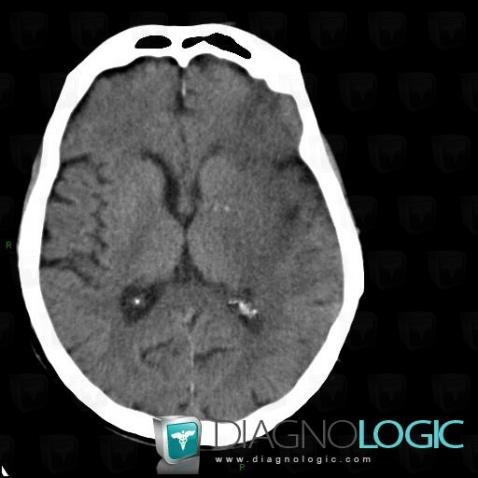

Cerebral infarction, Cerebral hemispheres, CT

Here is the specific information in the key image above:

- Diagnosis Cerebral infarction, Location(s) Cerebral hemispheres, with gamuts Hypodense intracerebral lesion on noncontrast CT